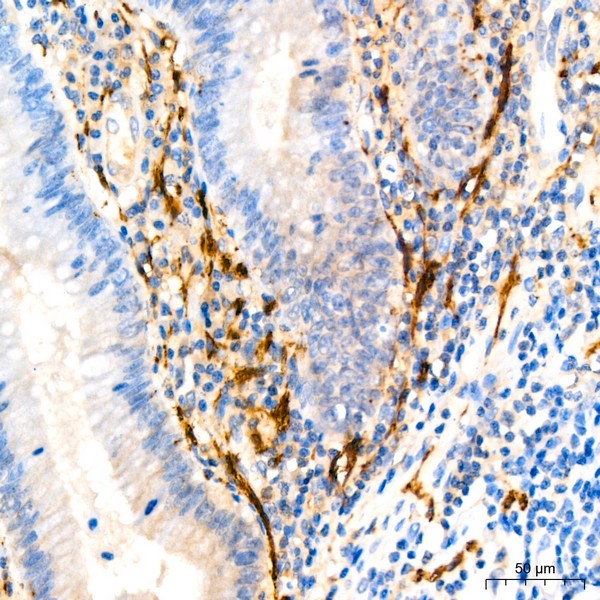

Immunohistochemistry analysis of Calretinin in paraffin-embedded human appendix using Calretinin Rabbit mAb (A22010) at dilution of 1:200 (40x lens).Perform high pressure antigen retrieval with 10 mM Tris/EDTA buffer pH 9.0 before commencing with IHC staining protocol.